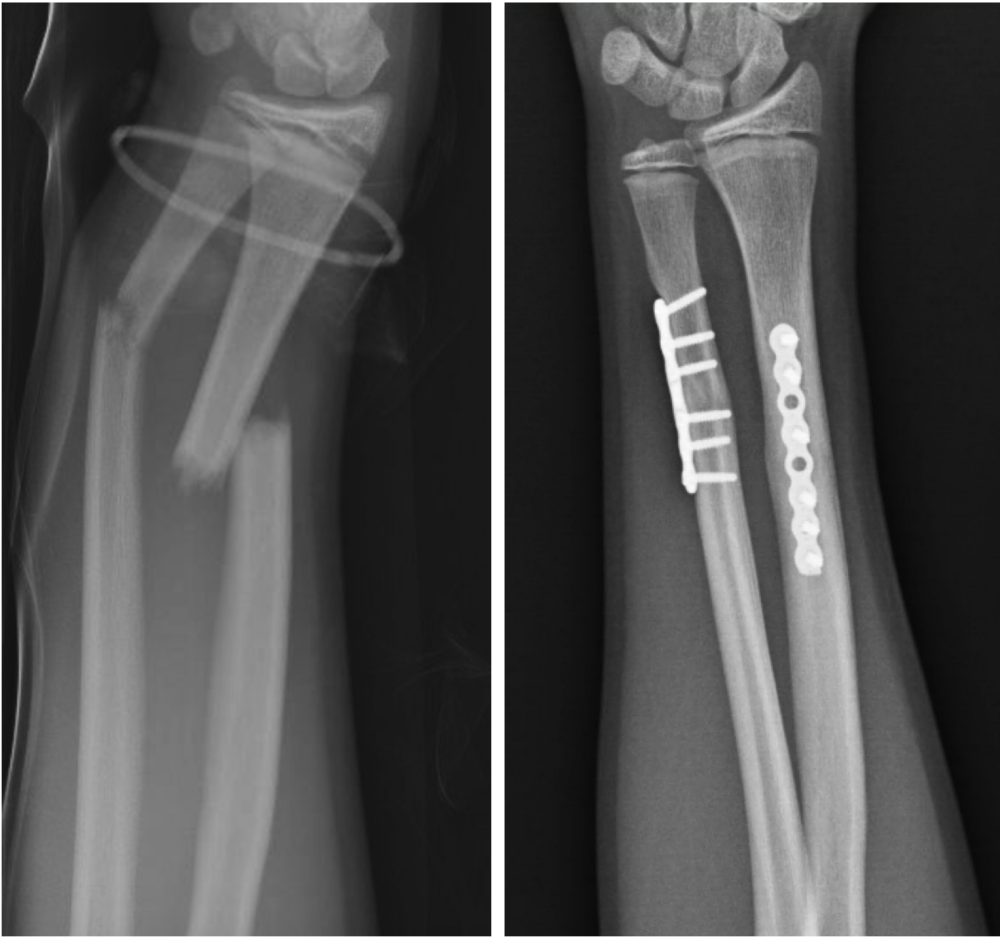

• Когда нужна операция перелома?

Когда нужна операция перелома?

Переломы обычно сопровождаются травмами других частей тела.Во всем процессе лечения пациентов необходимо лечить как единое целое.